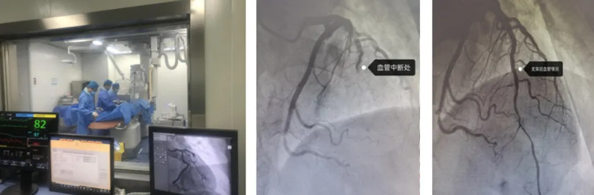

左:手术现场 中:血管中断处

右:介入支架后血管情况

急诊PCI手术要求高,难度大。由于患者高龄,心肌梗死面积大,又合并心力衰竭,当务之急是开通堵塞的冠状动脉,恢复血流灌注;而患者病情危重,不宜搬动,随时都有生命危险。心内二科立即协调开通绿色通道,为老人顺利完成急诊PCI手术,成功植入支架,恢复血流灌注,及时挽救了患者生命。